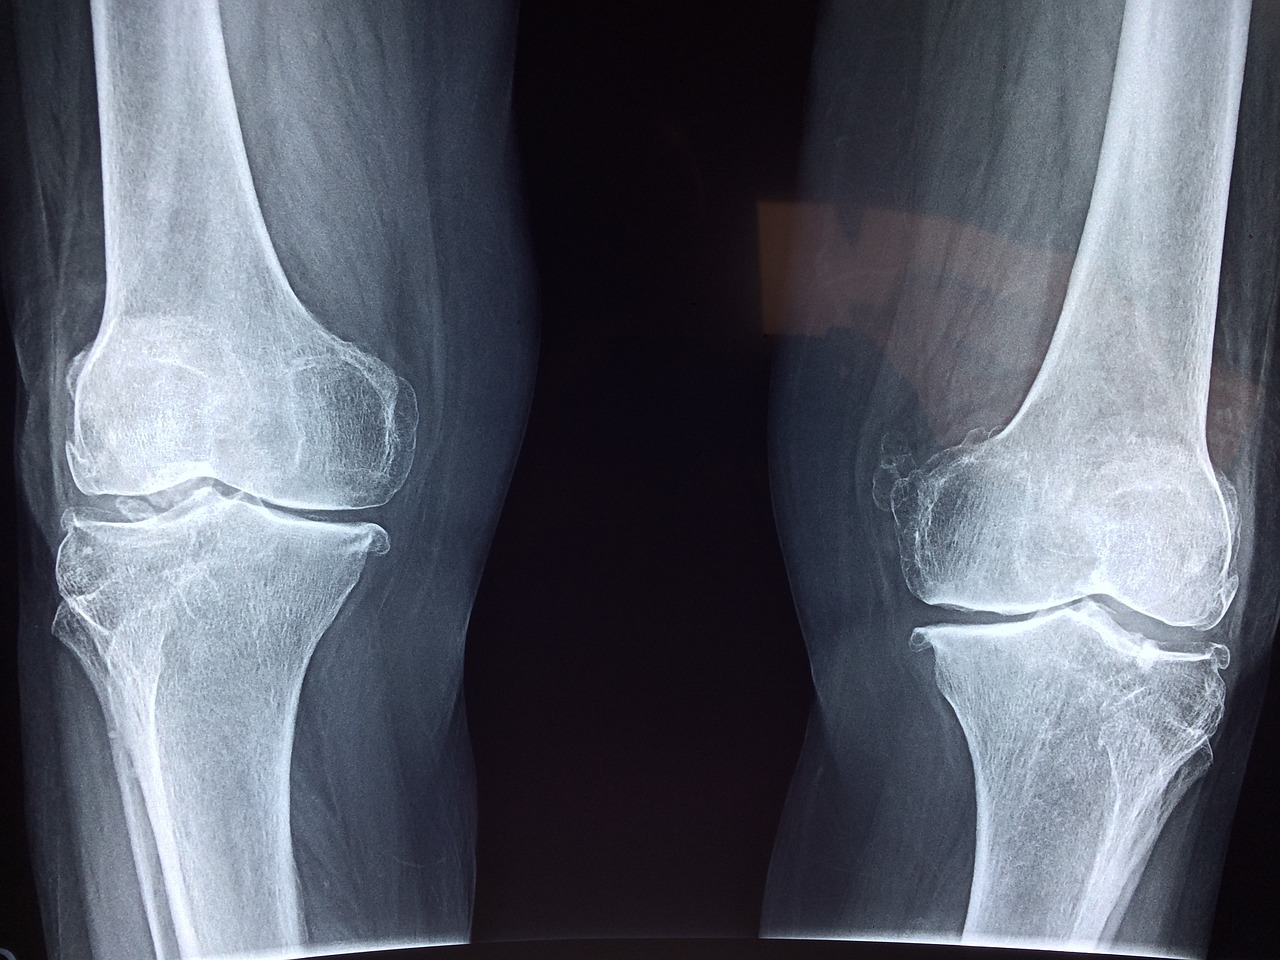

- Identify Types of Arthritis: Gain knowledge of the different types of arthritis, such as osteoarthritis, rheumatoid arthritis, and others, along with their common symptoms.

Arthritis is one of the most common conditions affecting adults, with millions of people worldwide experiencing its effects. As a massage therapist, having specialized knowledge in working with arthritic clients can make a significant difference in your practice. By understanding the nuances of this condition, you’ll be able to offer massage sessions that not only address pain and stiffness but also promote relaxation, improve mobility, and enhance overall well-being for your clients.